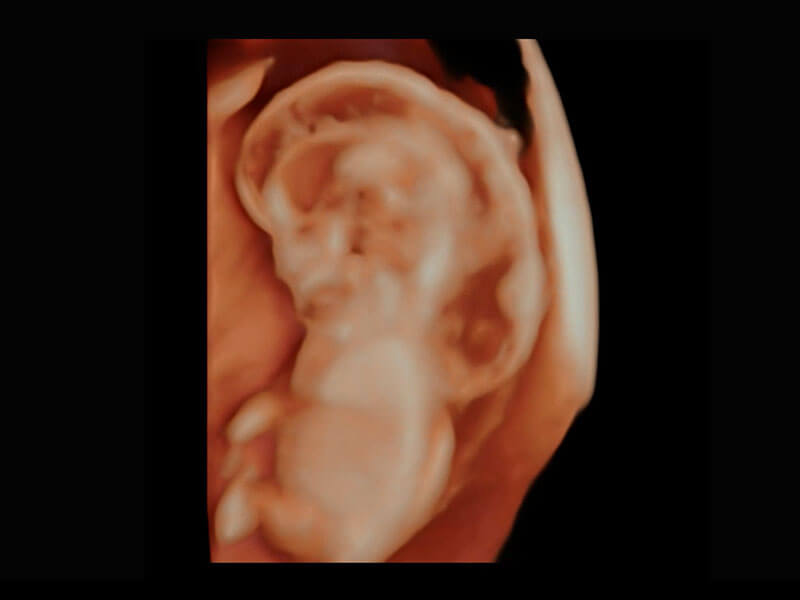

早孕筛查

P60在胎儿早孕期超声筛查中为您带来优异的图像质量。

• 高分辨率容积成像-早孕胎儿